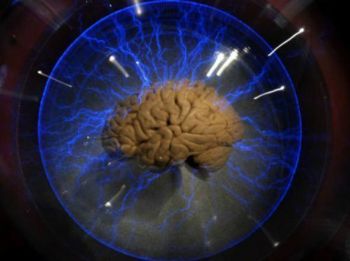

Estudo explica efeitos da abstinência de cocaína no cérebro

Um grupo de pesquisadores dos Estados Unidos descobriu parte do que acontece no cérebro, em nível celular, e que faz com que os dependentes em cocaína se sintam tão mal quando sofrem síndrome de abstinência, segundo estudo publicado na última segunda-feira.

Estudando ratos geneticamente modificados, os pesquisadores se concentraram em uma molécula, chamada receptor canabinoide tipo 1 ou CB1, que diminui a comunicação entre células nervosas.

Esta molécula é particularmente importante na área do cérebro conhecida como núcleo accumbens, que comanda as emoções e as motivações.

Já se sabia que a cocaína provoca forte efeito nesta área do cérebro. Mas este é o primeiro estudo a demonstrar o impacto da cocaína na produção de CB1 e o que isto representa na área do núcleo accumbes durante e depois de uma elevação provocada pela cocaína.